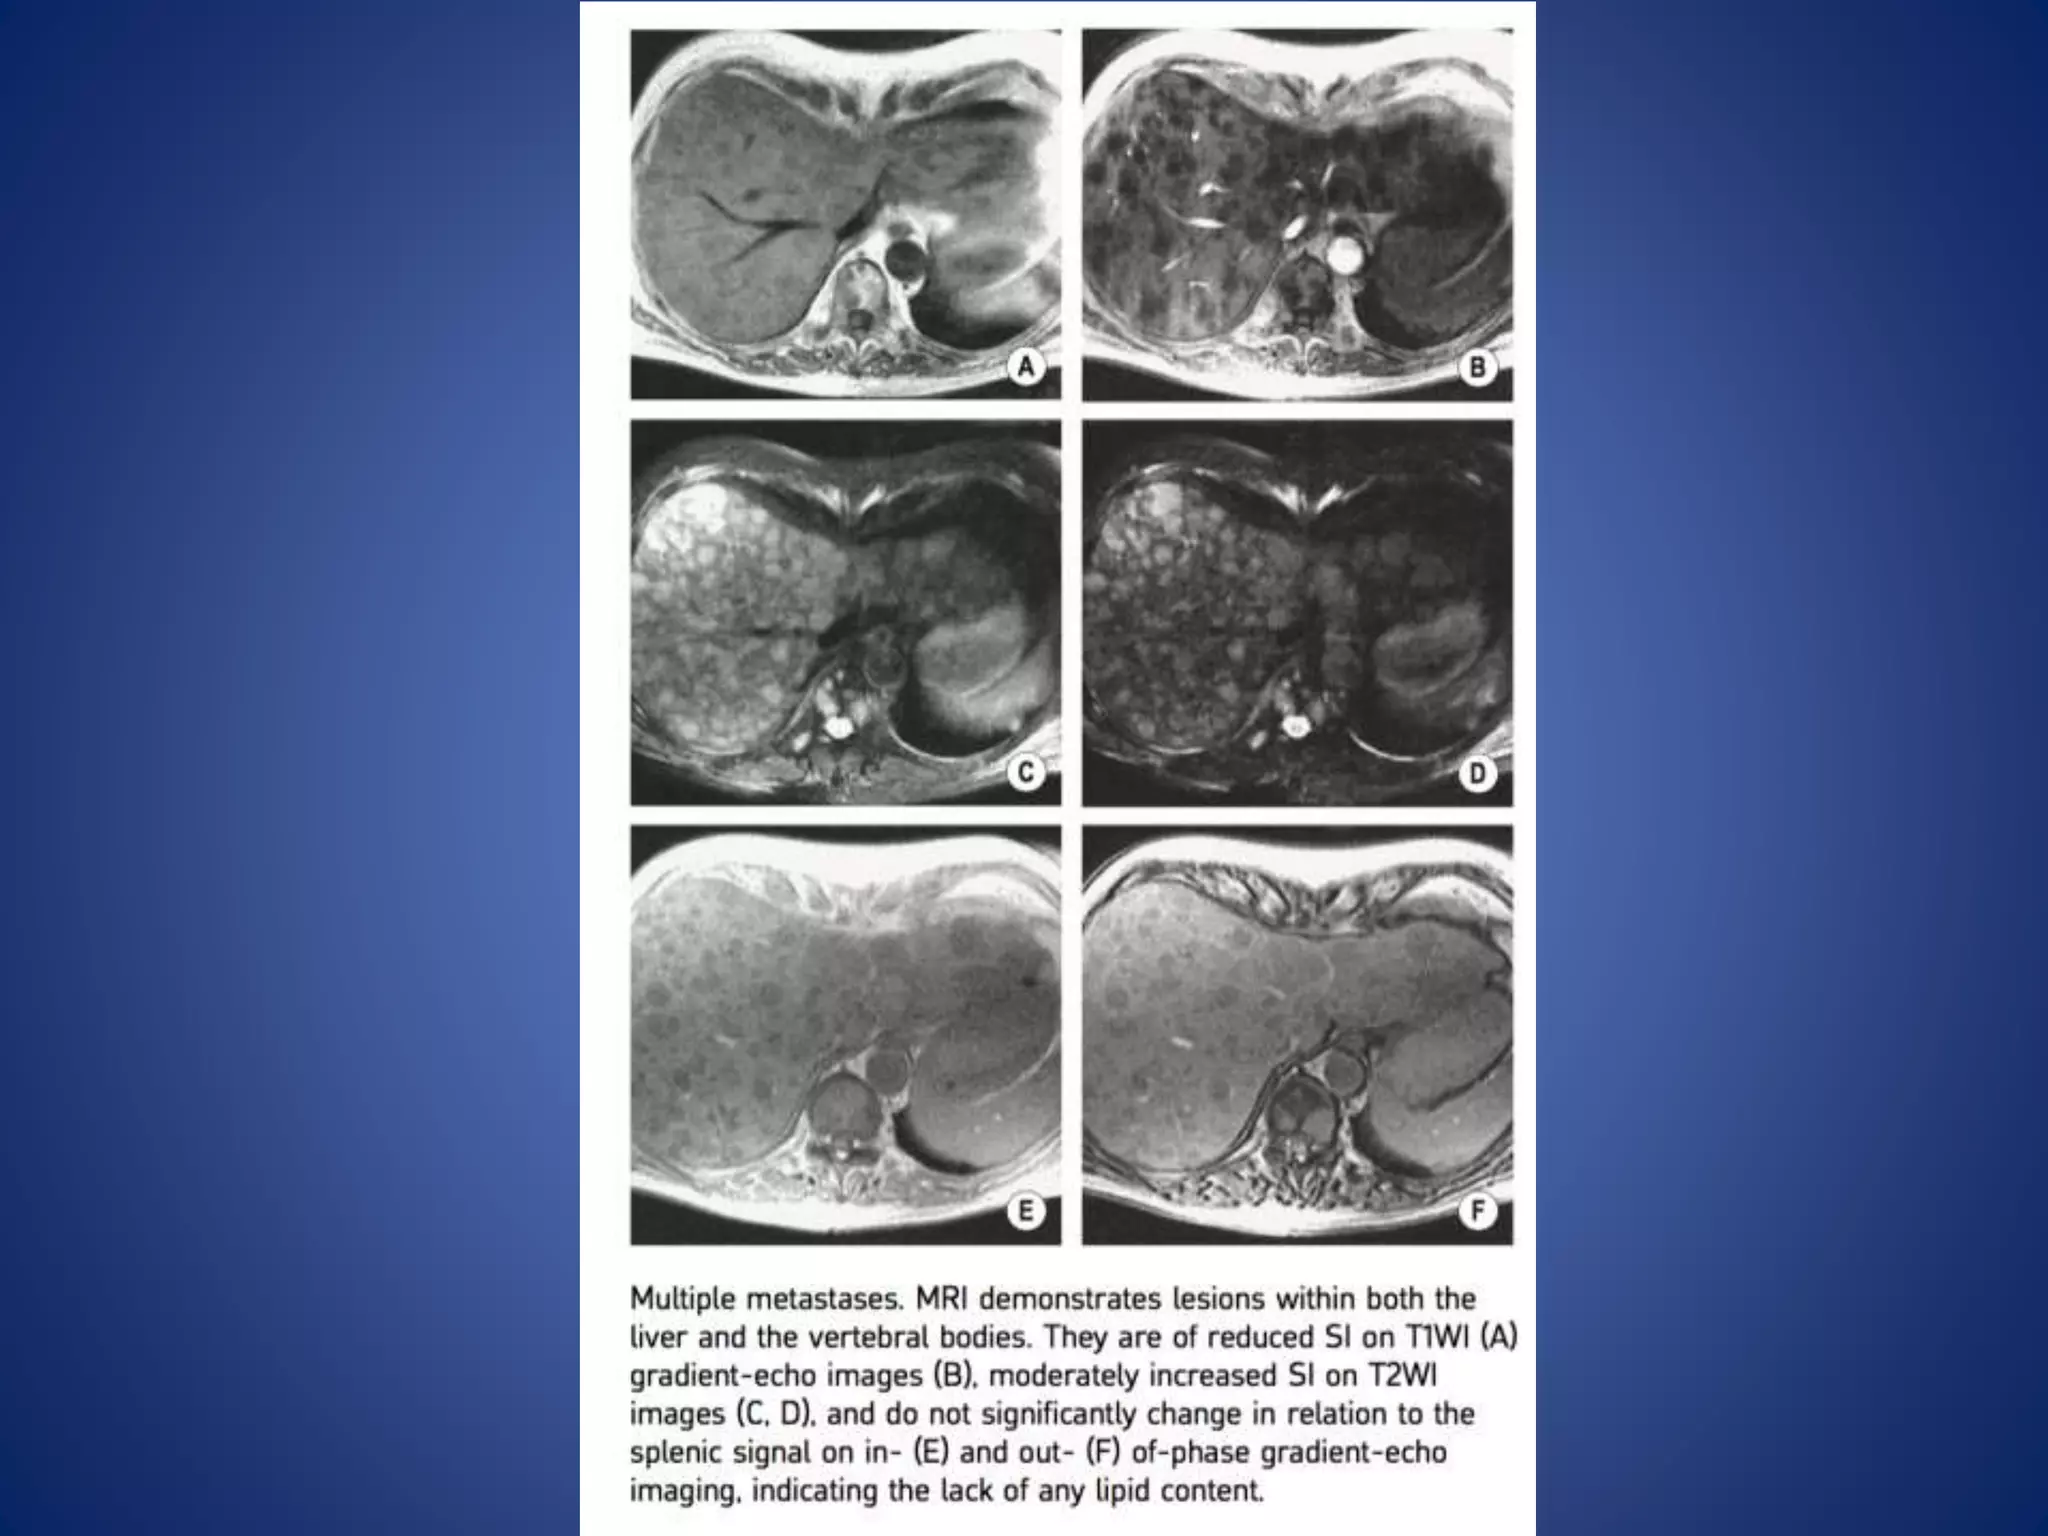

This document discusses various malignant liver lesions including hepatocellular carcinoma (HCC), liver metastases, and angiosarcoma. HCC is the most common primary liver cancer, often occurring in cirrhotic livers, and can appear solitary or multifocal on imaging. Liver metastases commonly spread from gastrointestinal or non-gastrointestinal primary cancers via the hepatic artery or portal vein. Angiosarcoma is a rare malignant vascular liver tumor associated with toxins like polyvinylchloride and arsenic.